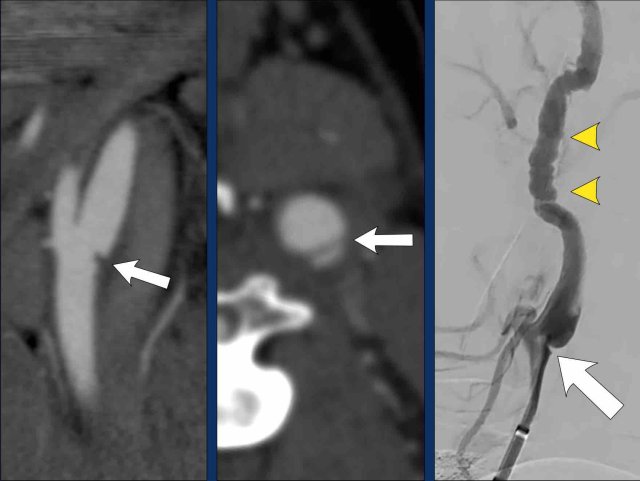

Floating Thrombus

On the saggital view there is a longitudinal filling defect

in the proximal internal carotid artery (arrowheads).

This filling defect is a

floating thrombus attached to a atherosclerotic plaque located at the carotid

bulb (white arrow).

In the axial plane this floatig thrombus causes a central filling defect in the ICA also now as a “donut sign” (arrowhead).

In case of an

accompanying intracranial occlusion of a large vessel endovascular therapy is

initiated to open this intracranial occlusion.

An isolated floating thrombus

(no large vessel occlusion) is treated with heparine or

anti-platelet therapy .

During the interventional procedure the flow was restored due to repositioning of the intimal flap caused by the catheter manipulation.

Carotid stent placement was considered but not

performed.

The patient was treated with Fraxiparine

After 24 hours there was a NIHSS: 2 with only a mild aphasia, after 3 months the NIHSS was down to 0.

Follow-up MRI after one month showed

a small left frontal infarction (white arrow).

The left ICA was patent and showed a remaining

of the intramural hematoma with high signal on the T1W-image (arrowhead).